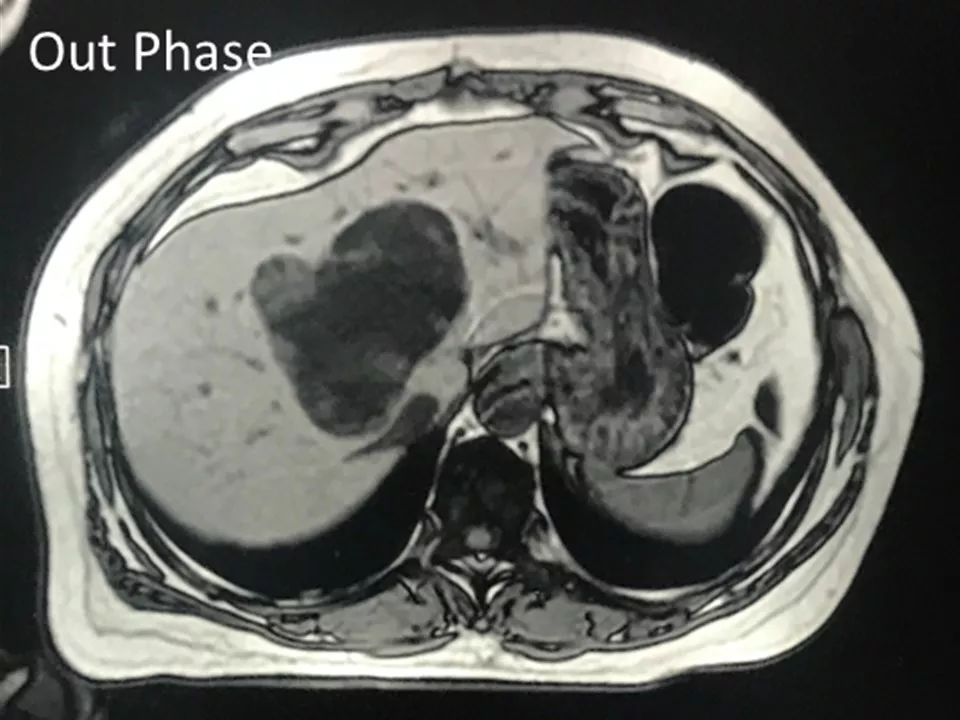

MRI表现:

肝内单发占位灶,累及肝左右叶及尾叶。T1WI示病灶以低信号为主,边缘多枚等信号结节,正反相位未见明显脂肪成份;T2WI示病灶以粘液成份为主呈高信号,边缘多枚稍高信号结节(相对肝实质),DWI呈不均匀等高信号,ADC图以高信号为主。动脉期病灶边缘均匀强化,壁结节显著强化,门脉期边缘仍持续强化,边缘光滑,壁结节呈相对等低信号。MRCP示胆管扩张,病灶与胆管相通。